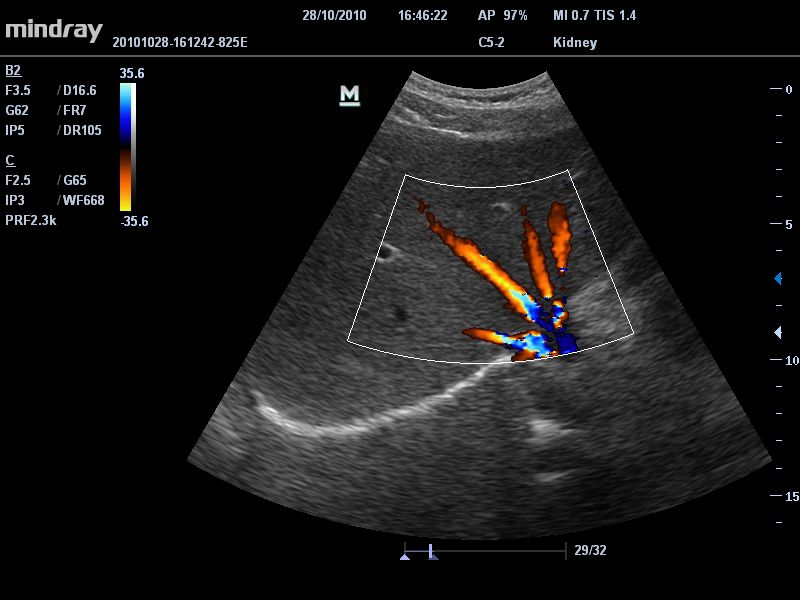

• Ультраректальный ветеринарный датчик Mindray 6LE5Vs